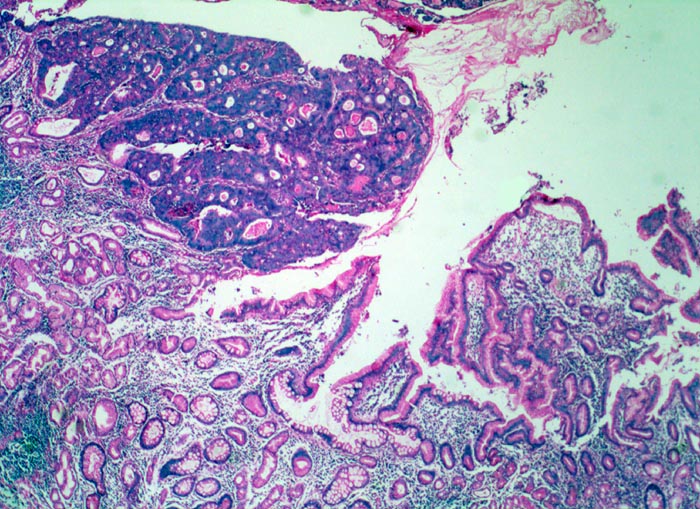

Morphologische Merkmale:

• Am unteren Ende des Präparates Antrummukosa mit mässiggradiger chronischer, geringgradig aktiver Gastritis und ausgedehnter intestinaler Metaplasie (Becherzellen).

• Weiter oben Invasion der Magenschleimhaut durch ein teils solides, teils drüsenbildendes Adenokarzinom mit stark atypischen Tumorzellen.

• Fokale Erosion des Karzinoms bedeckt von fibrinoleukozytärer Membran.

• Tumorinfiltration der Submukosa an der oberen Präparathälfte.

• Der invasive Karzinomanteil zeigt teilweise muzinöse Differenzierung (teils siegelringzellige Tumorzellen schwimmen in extrazellulären Schleimseen).

• Tumorfreie Lamina muscularis propria.